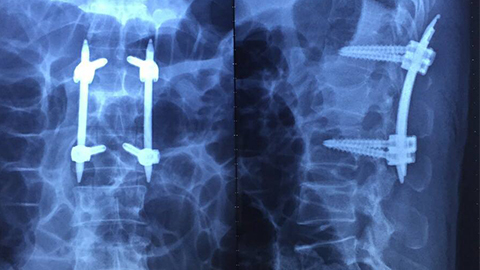

Bắt vít qua da cứu bệnh nhân chấn thương cột sống

Các bác sĩ Bệnh viện Xanh Pôn vừa thực hiện thành công kỹ thuật bắt vít cột sống qua da để cứu sống bệnh nhân bị tai nạn lao động.